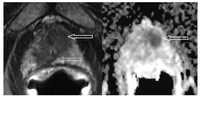

In unklaren Fällen, in denen die bisher erwähnten Untersuchungen keinen sicheren Karzinomnachweis erbracht haben, kann die Prostata mit der mpMRT (multiparametrische Kernspintomographie) der Prostata untersucht werden. Das mpMRT der Prostata hat zwischenzeitlich eine hohe Verbreitung erfahren, sodass es zunehmend in der Primärdiagnostik als auch im Verlauf bei active surveillance Strategie eingesetzt wird. Die Leitlinie formuliert inzwischen: Die mpMRT nach geltenden Qualitätsstandards sollte in der Primärdiagnostik eingesetzt werden.